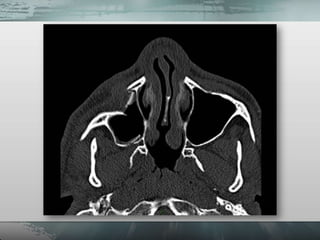

• Planigrafias.

– Incidência de Waters

– Incidência de Hirtz (Axial).

– Incidência para seios frontais (Caldwell).

– Incidência para ossos próprios do nariz

(perfil).

• Tomografia computadorizada.

• Planigrafias. – Incidência de Waters – Incidência de Hirtz (Axial). – Incidência para seios frontais (Caldwell). – Incidência para ossos próprios do nariz (perfil). • Tomografia computadorizada.